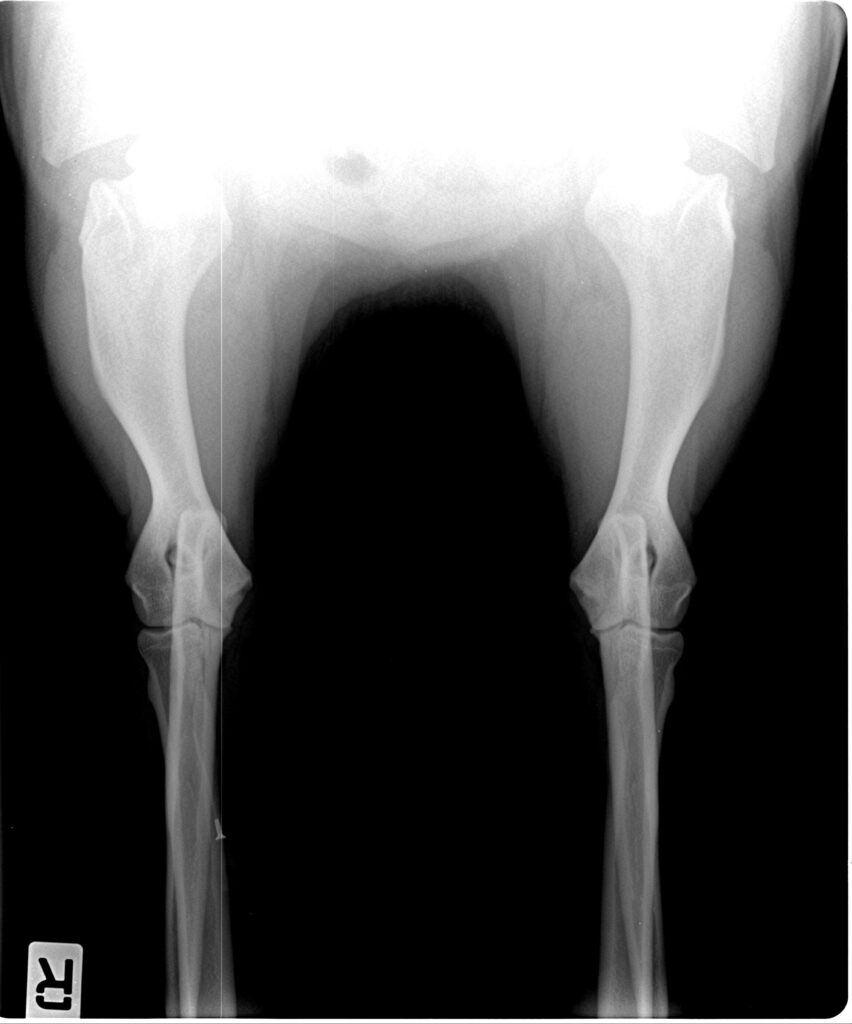

Röntgenaufnahmen

Ausgewählte Röntgenaufnahmen geben einen ergänzenden Einblick in die orthopädischen Untersuchungen dieses Zuchthundes. Die offiziellen Ergebnisse zu HD und ED finden Sie in der Übersicht oben. Weitere Nachweise stellen wir bei ernsthaftem Interesse gern zur Verfügung.